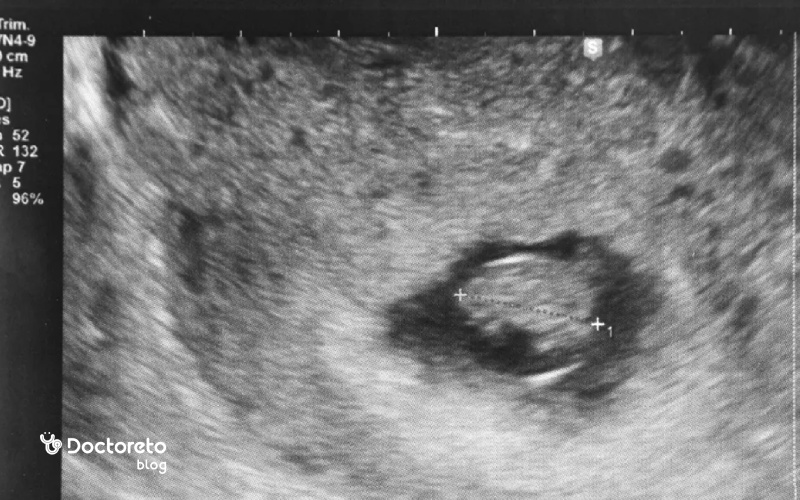

سونوگرافی هفته هفتم بارداری

در سونوگرافی هفته هفتم بارداری معمولاً ساک حاملگی، کیسه زرده و جنین بهطور واضح دیده میشوند. در این مرحله، پزشک رشد طبیعی جنین، محل قرارگیری ساک در رحم و وجود ضربان قلب را بررسی میکند. این سونوگرافی معمولاً از نوع ترانسواژینال است و دقیقترین روش برای تعیین سن بارداری و اطمینان از سلامت اولیه جنین محسوب میشود.

در هفته هفتم بارداری، اندازه جنین حدود ۵ تا ۱۲ میلیمتر (میانگین نزدیک به ۱ سانتیمتر) است و وزن او کمتر از یک گرم است. در سونوگرافی، جنین شبیه یک دانه لوبیا دیده میشود و سر او بزرگتر از بدن است. در این مرحله، قلب، مغز، ستون فقرات و جوانههای دستوپا در حال شکلگیریاند و رشد او با سرعت زیادی ادامه دارد.

اندازه نرمال crl در هفته هفتم

در هفته هفتم بارداری، قد سریـنشسته (CRL) جنین بهطور نرمال بین ۵ تا ۱۲ میلیمتر است. میانگین اندازه معمول حدود ۹ تا ۱۰ میلیمتر گزارش میشود. اندازهگیری CRL در سونوگرافی دقیقترین روش تعیین سن بارداری در سهماهه اول است. اختلافهای جزئی در مقدار CRL طبیعیاند و میتوانند به تفاوت در زمان لانهگزینی یا دقت تاریخ آخرین قاعدگی مربوط باشند.